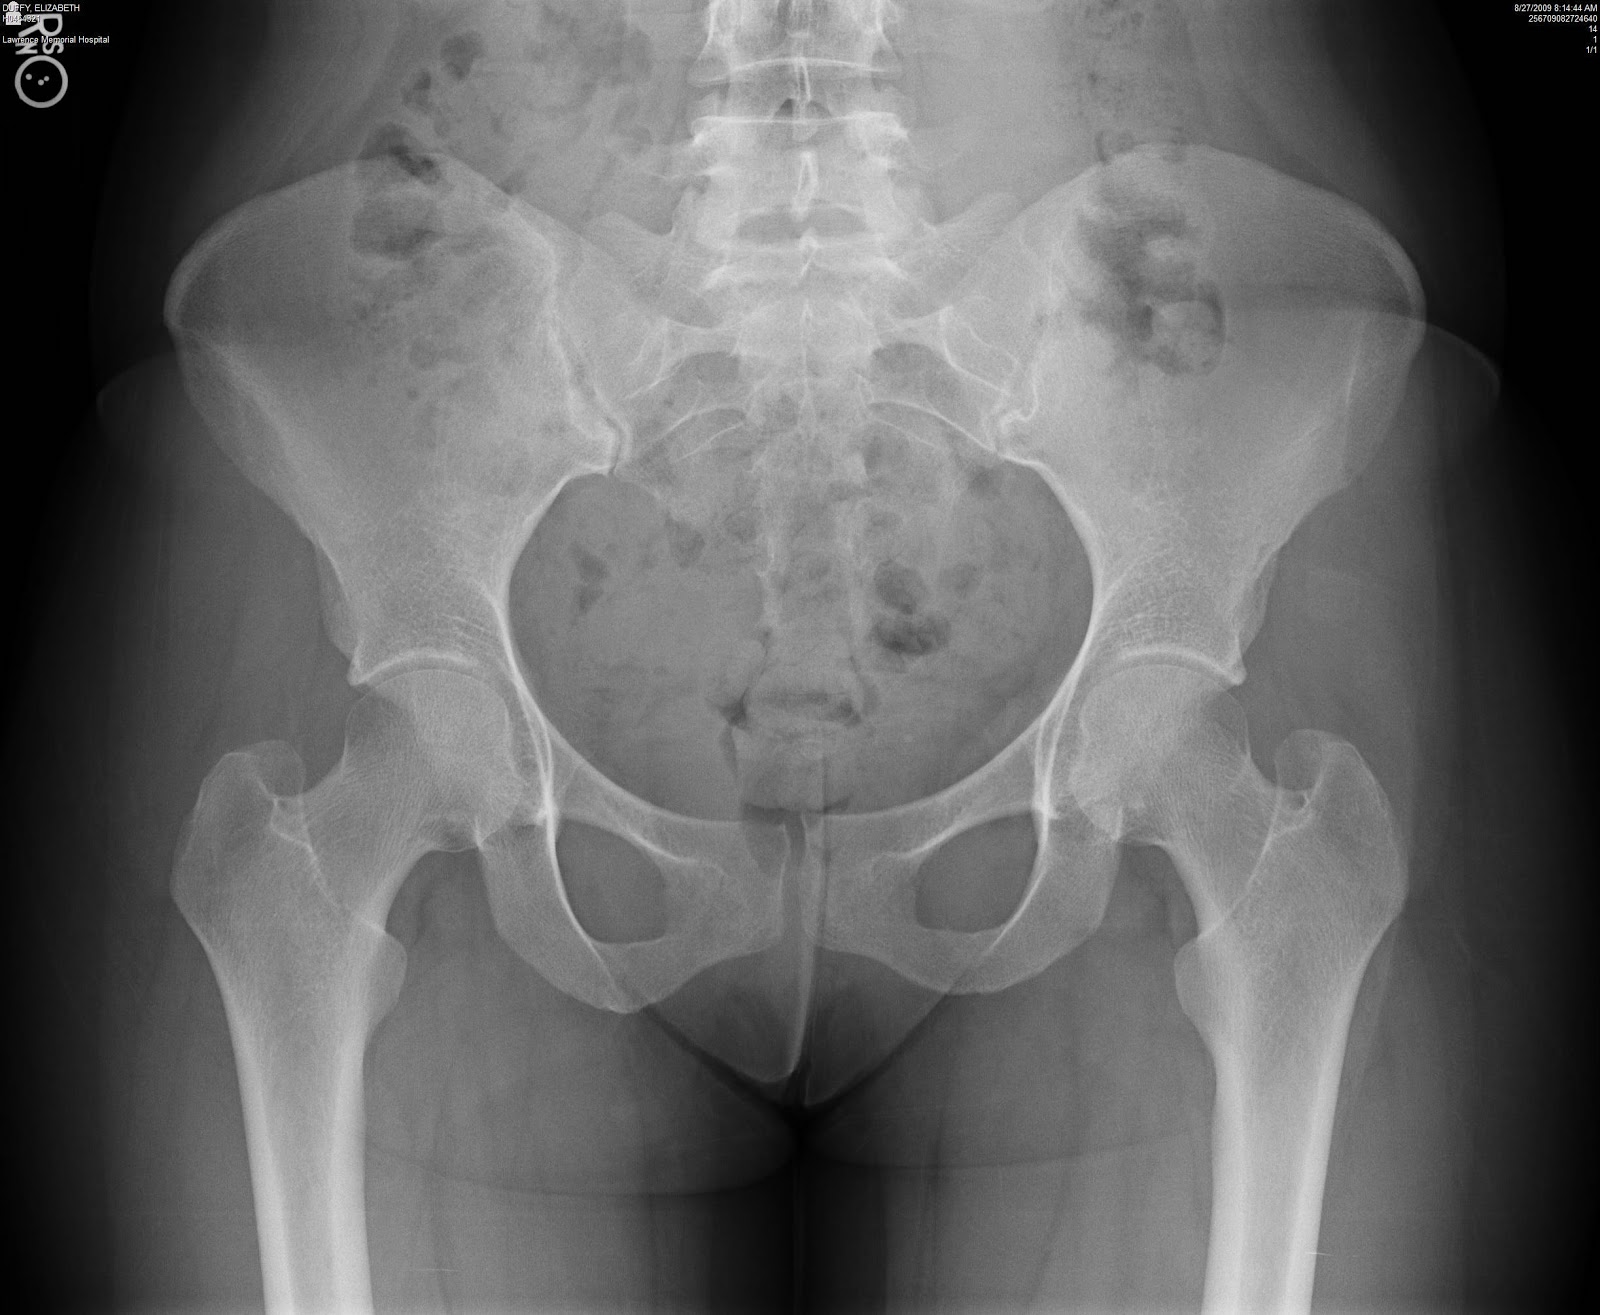

Рентген таза при миеломной болезни: Фотографии и Анализ